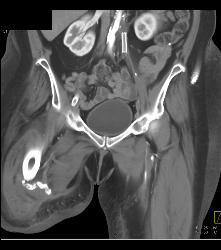

Ulcerations Thigh